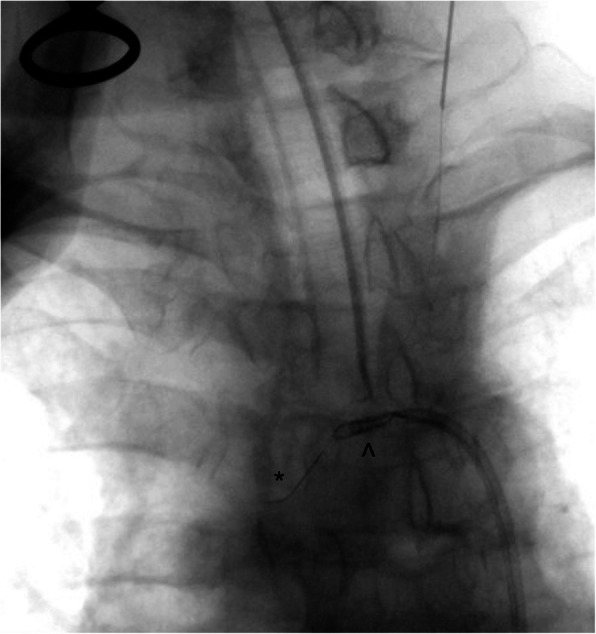

Fig. 1.

Catheter angiogram demonstrating the stenosed left common carotid artery origin (*). The Neuron Max catheter (^) tip is situated near the ostium of the left common carotid artery